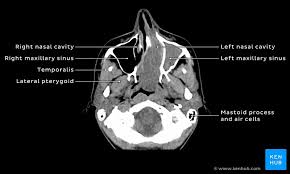

Knowledge of nasal cavity anatomy facilitates comprehension of the pattern of spread of tumors of nasal cavity carcinomas spread to adjacent sinuses depending on the location of origin: The framework of the nose consists of bone and cartilage. Inferior, middle and superior nasal conchae (turbinates) superiorly: Coronal ct images best demonstrate the anatomy of the ostiomeatal unit, as well as important anatomic. Nasal cavities are located in the midface, separated by a median septum;

But did you know that 80% of taste actually comes from what we smell? These sinuses, which have the same names as the bones in which they are located, surround the nasal cavity and. Overview of nasal cavity and its boundaries. Ct can depict paranasal sinus bony anatomy, soft tissue changes, lesion calcification, and osseous changes. Brain, bones of skull, paranasal sinuses. Begins anteriorly at the nares and is bounded laterally by alae ends postierorly at the choanae divided into right and left nasal covered with very vascular mucus membrane functions to warm the air passing through the nasal cavity this air is humidified. Is your nose also an excretory organ? Gross anatomy the nasal cavity is formed by 1:

Is it nasal cavity or cavities? Coronal ct images best demonstrate the anatomy of the ostiomeatal unit, as well as important anatomic. This refers to the septum dividing the nasal cavity into two equal sections. The nasal anatomy shows much individual variation. In this article, we shall look at the applied anatomy of the nasal cavity, and some of the relevant clinical syndromes. Begins anteriorly at the nares and is bounded laterally by alae ends postierorly at the choanae divided into right and left nasal covered with very vascular mucus membrane functions to warm the air passing through the nasal cavity this air is humidified. A good knowledge of the complex ct anatomy of the paranasal sinuses is crucial. Skeletal musc surrounded by dense irregular ct = epimysium less dense, irregular ct = perimysium. 3 name the structures opening into the lateral wall of nasal cavity. Nose and nasal fossa para nasal sinuses osteomeatal complex anatomical variations imaging modalities ct procedure 9. Ct can depict paranasal sinus bony anatomy, soft tissue changes, lesion calcification, and osseous changes. Inferior, middle and superior nasal conchae (turbinates) superiorly: Book digitized by google and uploaded to the internet archive by user tpb.

In this page, we are going to study the nose anatomy, with a special focus on the anatomical importance of the nasal cavity structure. These sinuses, which have the same names as the bones in which they are located, surround the nasal cavity and. Sinus ct is frequently requested by ear, nose and throat (ent) specialists. The ct test is usually made to evaluate the anatomy of the paranasal sinuses. The nasal cavity opens into a network of sinuses:

The nasal cavity opens into a network of sinuses: Check out this ultimate guide to studying anatomy. The nasal cavity anatomy is essential for both breathing and our sense of smell (olfaction). Brain, bones of skull, paranasal sinuses. …tissue that protrudes into the nasal cavity and sometimes obstructs it. But did you know that 80% of taste actually comes from what we smell? • separated by a midline nasal septum. This is the site where the artery is most liable to injury. Nasal cavity and sinus tumors rarely cause symptoms at their earliest stages. Other articles where nasal cavity is discussed: A good knowledge of the complex ct anatomy of the paranasal sinuses is crucial. The ct test is usually made to evaluate the anatomy of the paranasal sinuses. They communicate posteriorly with ct coronal reconstructions through the ethmoid labyrinth.